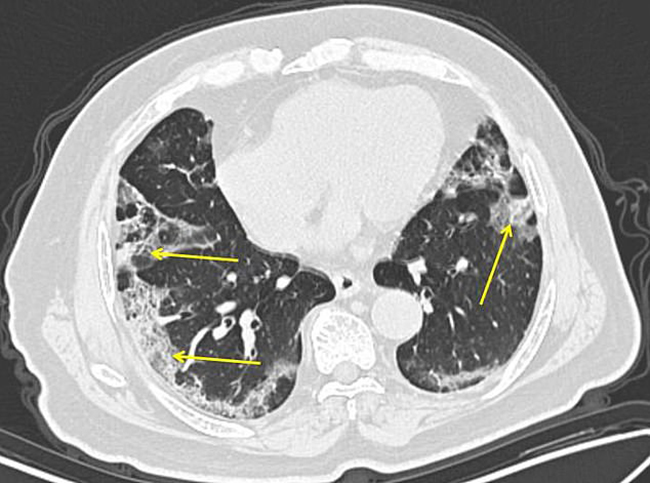

Ảnh chụp bệnh nhân 65 tuổi, người từng đến Vũ Hán. Quét CT được thực hiện 11 ngày sau các triệu chứng xuất nhiễm Covid-19 xuất hiện. Các tổn thương mờ có hình dạng tròn xuất hiện nhiều trên phổi. (Ảnh: Dailymail)

Bệnh nhân nam 29 tuổi không có tiền sử phơi nhiễm, xuất hiện sốt và ho, phải nhập viện điều trị tích cực. Hình A: Chụp CT không tương phản cắt dọc trục cho thấy có rất nhiều đốm trắng trong phổi và bề mặt phổi loang lỗ. Hình B: Ở thùy giữa và thùy phải cùng vùng ngoại vi xuất hiện rất nhiều mảng trắng, điều này chứng tỏ virus Corona đang xâm chiếm và phá hủy phổi. (Ảnh: Itnonline)